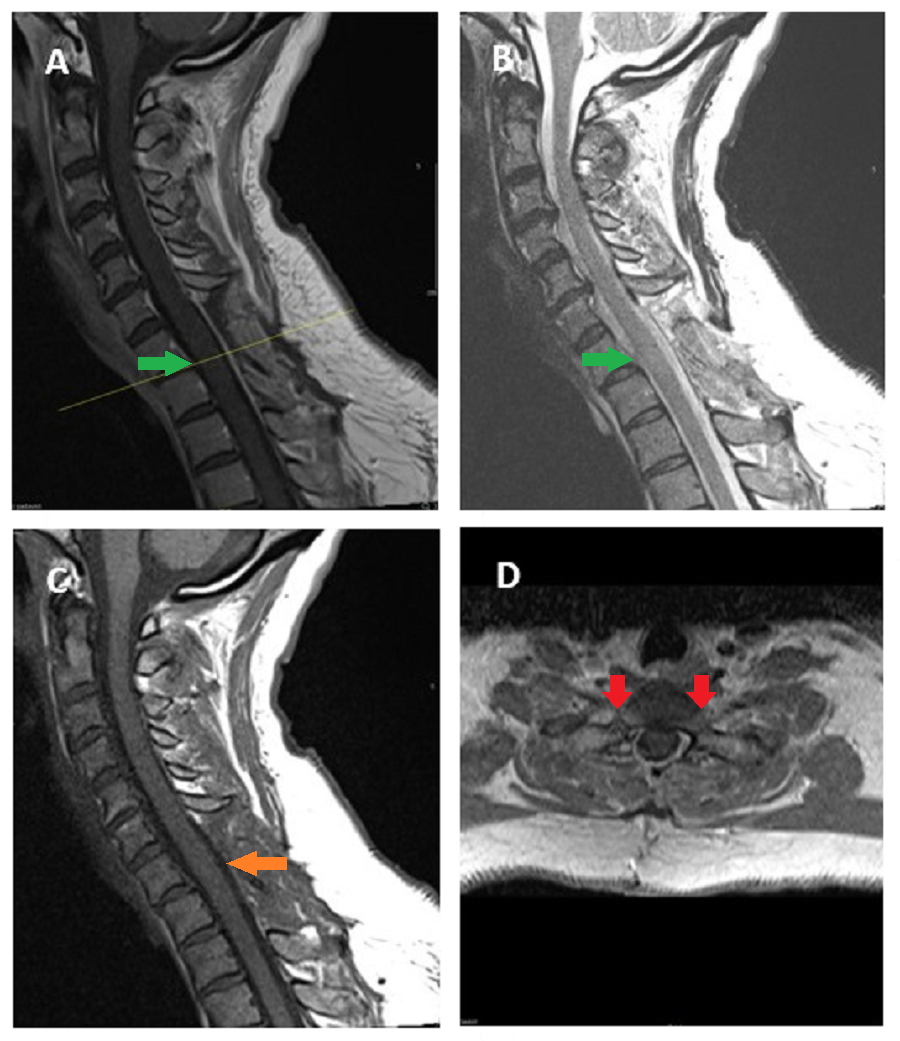

Cureus Bilateral Synovial Cysts As A Rare Cause Of Myelopathy In A 38 Year Old Woman